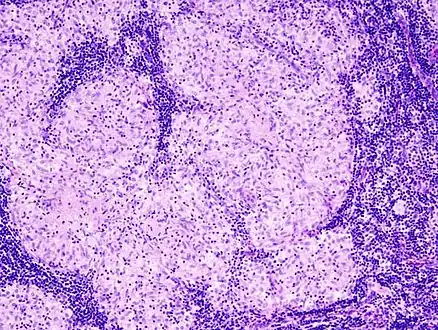

Sarcoidosis is characterized by the formation of non-necrotizing ("non-caseating") granulomas in various organs and tissues.[96] Giant cells, specifically Langhans giant cells, are often seen in sarcoidosis.[97] Schaumann bodies seen in sarcoidosis are calcium and protein inclusions inside of giant cells as part of a granuloma.[98] Asteroid bodies can be seen in sarcoidosis.[98] Hamazaki–Wesenberg bodies can be seen in lymph nodes and more rarely in lung biopsies with sarcoidosis and are inclusion bodies of lysosomes with protein, glycoprotein and iron.[99]

Sarcoidosis in a lymph node

Schaumann body in sarcoidosis

Asteroid body in sarcoidosis

Hamazaki–Wesenberg bodies in sarcoidosis in lymph node